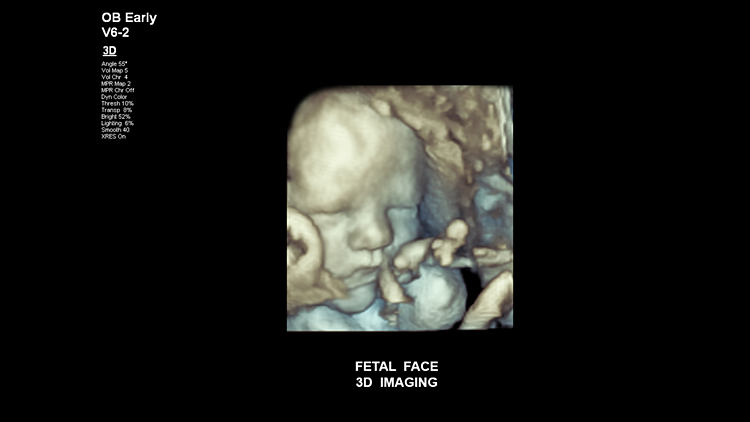

3D реконструкция лица плода, V6-2